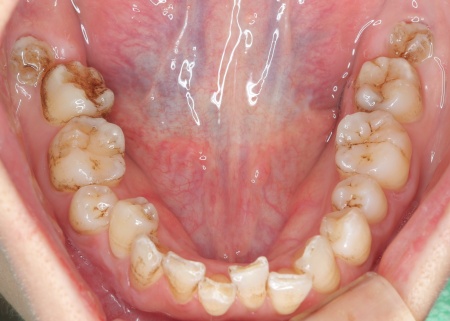

拝見したところ、歯が全体的にずれたりねじれたりして生えており、歯並びがデコボコしていました。 また、数本の歯にはプラスチックの詰め物が装着されていましたが、経年的な劣化により歯との間に段差が生じています。これも噛み合わせのバランスを崩す原因のひとつになっていると考えられました。 歯並びや噛み合わせの乱れをこのまま放置すると、歯磨きがしにくくなり虫歯や歯周病のリスクが高まるほか、特定の歯に強い力がかかり続けることで将来的に歯の寿命に影響を及ぼすおそれもあります。

診断結果を踏まえ、まずはワイヤー矯正で歯並びと噛み合わせを整え、その後に形が変化している歯や劣化した詰め物を白いセラミック素材で作り直す治療計画を提案し、同意いただきました。 この治療方法であれば、歯を動かして噛み合わせの位置関係をしっかりと整えたうえでセラミックによる修復治療を行えます。また金属を使用しない白い素材を用いるため、見た目の違和感を抑えられます。 また、下の左右に半分埋まっている親知らず(第3大臼歯)があるため、矯正治療の際に抜歯する必要があることをお伝えし、ご了承いただきました。 まず親知らず2本を抜歯し、ワイヤー矯正治療から開始します。

治療前